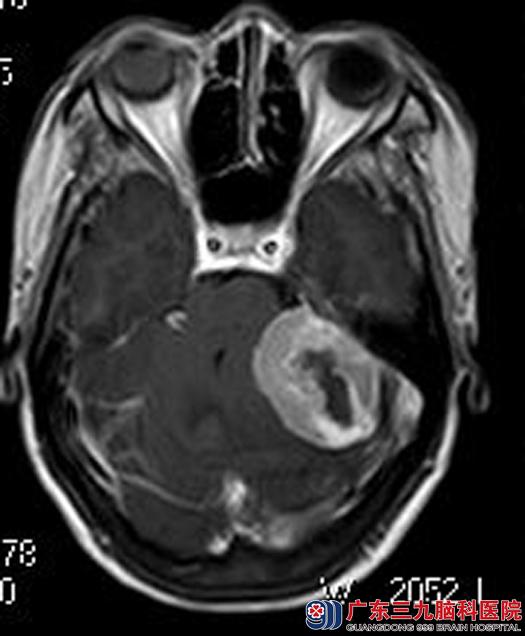

孩子们大了后,觉得母亲这么痛苦,总该要去医院找找原因。当地医院行头颅CT检查提示桥小脑角占位,考虑脑肿瘤。这么长时间的头痛是因为脑袋里有肿瘤,子女们觉得母亲是为了他们才耽误了病情,急急忙忙地带着她来到广东三九脑科医院。头颅MR检查,结果提示左侧桥小脑角区占位,大小约44.4mm×31.0mm×41.5mm,考虑脑膜瘤可能性大。

▲手术前